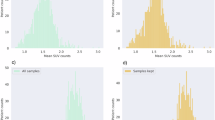

AD dataset

Both NBV and BV were affected by FFR processing, in terms of both variability and systematic differences. In Fig. 3, an example of effected SIENAX by FFR processing is given. Figure 4 a and b show scatter plots of NBV and BV for FFR-processed images versus full images in the AD dataset; corresponding Bland-Altman plots are provided in the supplementary section. These results suggest that FFR affected NBV variability more than BV variability, which is confirmed by the ICCs (Table 4): absolute agreement of NBV between FFR-processed images and full images ranged from 0.715 (Defacing) to 0.896 (FaceMasking), while for BV, absolute agreement ranged from 0.933 (Defacing) to 0.982 (QuickShear). Pairwise comparisons showed that NBV was typically overestimated after processing data with QuickShear (median [1st and 3rd quartiles] 1.26 [− 4.40; 8.62] mL) and FaceMasking (5.91 [− 1.57; 16.38] mL), and underestimated after Defacing (− 2.17 [− 10.80; 7.81] mL). BV was typically underestimated after FFR, with median [1st and 3rd quartiles] volume differences of − 2.44 [− 5.11; − 1.22] mL (QuickShear), − 0.52 [− 2.47; 1.10] mL (FaceMasking), and − 7.60 [− 12.13; − 4.71] mL (Defacing). The supplementary section provides means and standard deviations.

Scatter plots of the normalized brain volume (a), brain volume (b), white matter lesion volume (c), and glioblastoma volume (d). The facial removal datasets are plotted against the full scan; QuickShear, blue diamond; FaceMasking, red cross; and Defacing, green plus sign. All scatter plots have an identity line indicating perfect agreement. NBV, normalized brain volume; BV, brain volume; FFR, facial features removal; WMLV, white matter lesion volume; GBV, tumor volume; mL, milliliter; L, liter

MS dataset

For WMLV, absolute agreement between FFR-processed images and full images was high, but there were small but significant systematic differences. In Fig. 5, an example of affected lesion segmentation by FFR processing is given. Figure 4c shows the WMLV scatter plot; corresponding Bland-Altman plots are provided in the supplementary section. The corresponding ICCs in Table 5 are all ≥ 0.988. The median [1st and 3rd quartiles] WMLV values after FFR were 2.94 [1.35; 8.12] mL (QuickShear), 3.15 [1.60; 8.15] mL (FaceMasking), and 2.77 [1.21; 7.77] mL (Defacing). For the full image, the WMLV value was 2.71 [1.32; 7.76] mL. In the case of FaceMasking, the WMLV is significantly higher than the WMLV of full images, Bonferroni-corrected p < 0.001. The supplementary section provides means and standard deviations.

Glioblastoma dataset

GBV appeared to be the outcome measure that is most strongly affected by FFR, with low to poor agreement and systematic volume underestimation after FFR by FaceMasking. In Fig. 6, an example of affected glioblastoma segmentation by FFR processing is given. The scatter plot in Fig. 4d, the corresponding Bland-Altman plots in the supplementary section, and the ICCs in Table 5 show that FFR was affected, irrespective of tumor size. ICCs of 0.843, 0.312, and 0.810 between the full and FFR-processed images for QuickShear, FaceMasking, and Defacing indicate substantial effects of FFR. GBV were lower after FFR: differences with full image values were − 2.46 [− 7.08; − 0.54] mL (QuickShear), − 1.31 [− 7.74; 0.57] mL (FaceMasking), and Defacing − 3.28 [− 8.16; − 0.72] mL (Defacing). The supplementary section provides means and standard deviations.